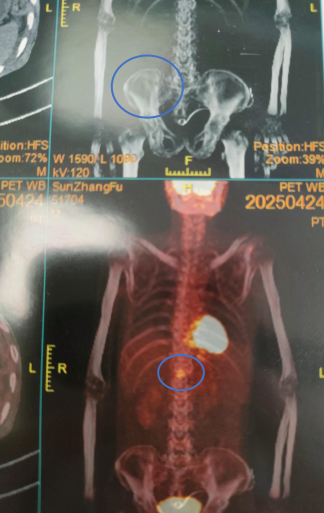

为进一步明确诊断,患者于2025年4月转至本院消化内科。腹部CT示肝脏外形大小尚可,脾厚约5.2 cm。肝脏CTA示食管下段、胃底壁和腹膜后无曲张静脉,下腔静脉和肝静脉未见异常狭窄,无充盈缺损。

图2. 腹部B超